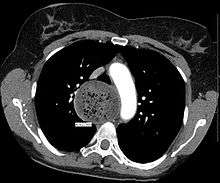

A chest X-ray showing achalasia ( arrows point to the outline of the massively dilated esophagus ) | |